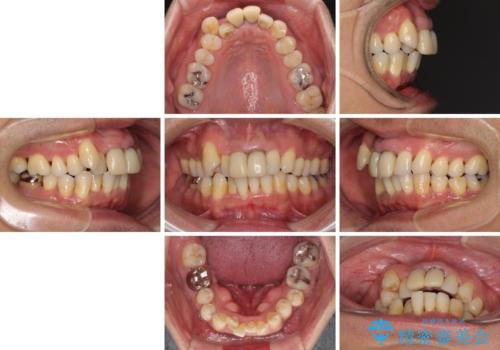

- 八重歯を気にして来院された患者様です。

上顎前歯の突出感と右上の八重歯を気にされていたので、上顎左右の第一小臼歯2本を抜歯し、ワイヤー装置にて矯正治療を行うこととしました。

上顎前歯に装着されていた保険診療の前歯は見た目が気になるとのことであったので、矯正治療後にオールセラミッククラウンにて補綴治療を行うこととしました。

食いしばりにより奥歯がすり減っており、咬み合わせが定まるまで時間がかかりましたが、整った口もに仕上がりました。